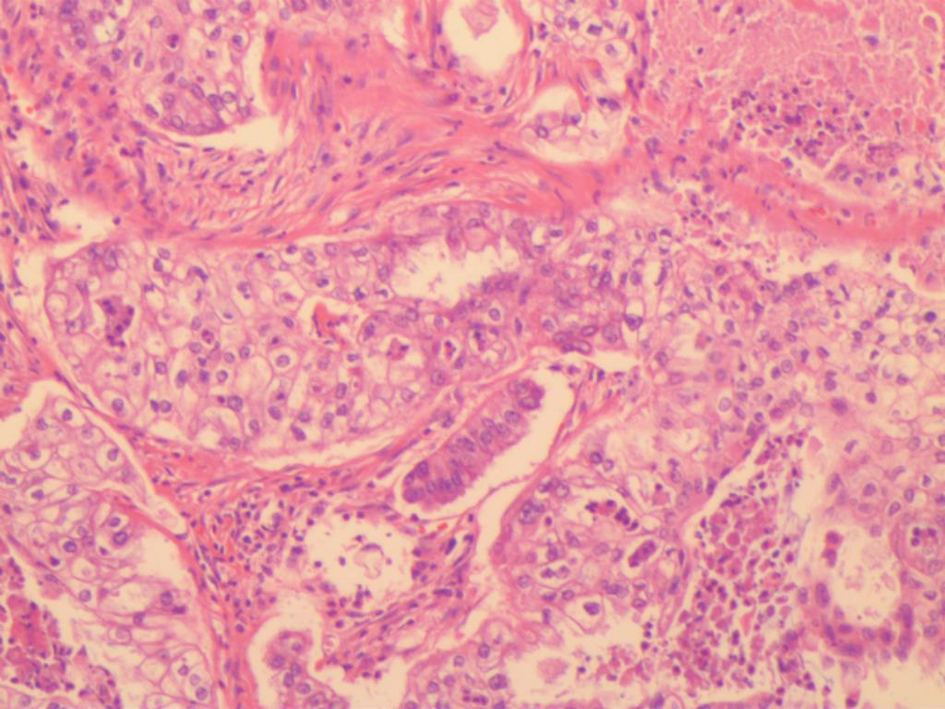

Primary clear cell carcinoma of the gallbladder: A case report

2023, 39(4): 901-903. DOI: 10.3969/j.issn.1001-5256.2023.04.023

Abstract(637) HTML (292) PDF (1992KB)(64)

Abstract: